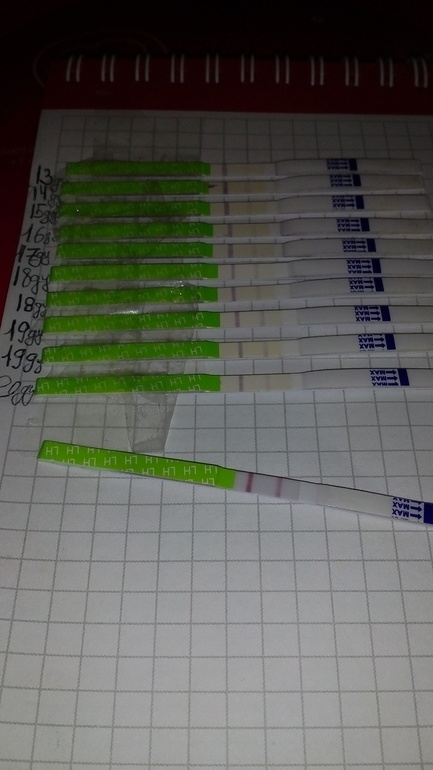

Девочки кто разбирается?была ли о? есть ли шанс на б в этом цикле?

Девочки кто разбирается?была ли о? есть ли шанс на б в этом цикле?

Скажите пожалуйста девочки это О? Или ещё должна быть темнее?